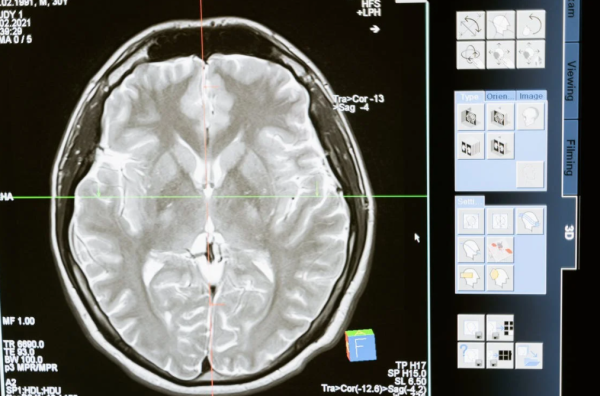

一根头发一样细的光纤有望用于患者大脑的微创深层组织研究,以显示阿尔茨海默病和其他脑部疾病的影响。该研究可以为实验室研究中的微创体内脑成像奠定基础,并随着时间的推移监测神经系统疾病患者的神经元活动。

该技术用于成像脂褐质,一种与年龄相关的荧光色素,随着时间的推移作为代谢废物在体细胞中积累,体细胞是包含细胞核的神经元部分,负责神经递质的产生。脂褐质的异常积累可能与阿尔茨海默病的进展有关,尽管对该过程知之甚少。

通过荷兰脑库获得的阿尔茨海默氏症患者供体的脑组织样本中可以看到色素堆积。